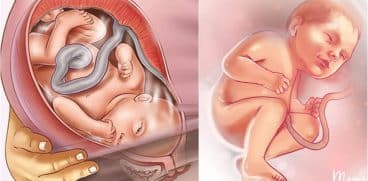

Saptamana 27 de sarcina marcheaza sfarsitul celui de-al doilea trimetru de sarcina. In aceasta faza, plamanii si creierul copilului continua sa se dezvolte.

Totusi, creierul lor este activ acum, iar unii specialisti sunt de parere ca bebelusul poate chiar visa atunci cand doarme in uterul mamei sale.

Plamanii nu sunt complet dezvoltati, insa pot functiona cu ajutor medical, in situatia unei nasteri premature. Cert este ca un copil nascut in saptamana 27 de sarcina va fi capabil sa supravietuiasca.

De asemenea, ochii copilului se deschid si inchid, isi poate suge degetul si doarme si sta treaz la intervale regulate.

La finalul saptamanii 27 de sarcina, copilul va masura 36.6 cm si va cantari 875 de grame. Practic, este de dimensiunea unei conopide.